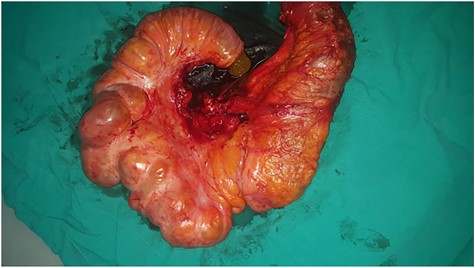

Excisional biopsy of the mass with part of the ascending colon.

On macroscopic examination, the ileal mass showed multiple mucosal diaphragms dividing the ileum into compartments. The cut surface of the terminal ileum revealed narrowing of the lumen and small polypoid thickness (Fig. 4).

The cut surface of the terminal ileum reveals narrowing of the lumen and small polypoid thickness.